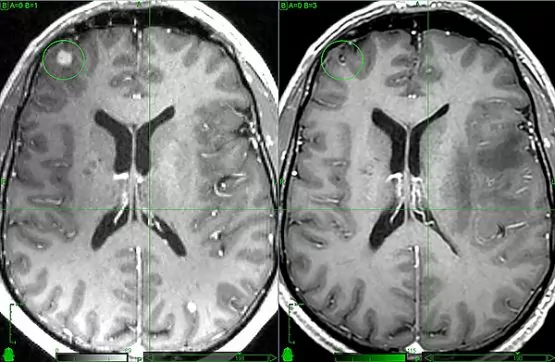

K diagnostice metastáz postihujících mozek se používají moderní diagnostické metody jako CT nebo MRI. V tomto případě se MRI provádí s kontrastem. Je třeba si uvědomit, že čím dříve bude stanovena diagnóza a zjištěny metastázy, tím dříve budou moci specialisté pacientovi předepsat individuální léčebný plán, který bude využívat co nejšetrnější terapeutické postupy. Navíc existuje reálná šance dosáhnout určité regrese neurologických příznaků.

- Zobrazování magnetickou rezonancí. Při provádění MRI dostává lékař vrstvené obrazy vnitřních orgánů vysoké úrovně kvality a přesnosti. Po vyšetření pomocí PC a různých nainstalovaných programů jsou informace zpracovány a diagnostikována specialisty.